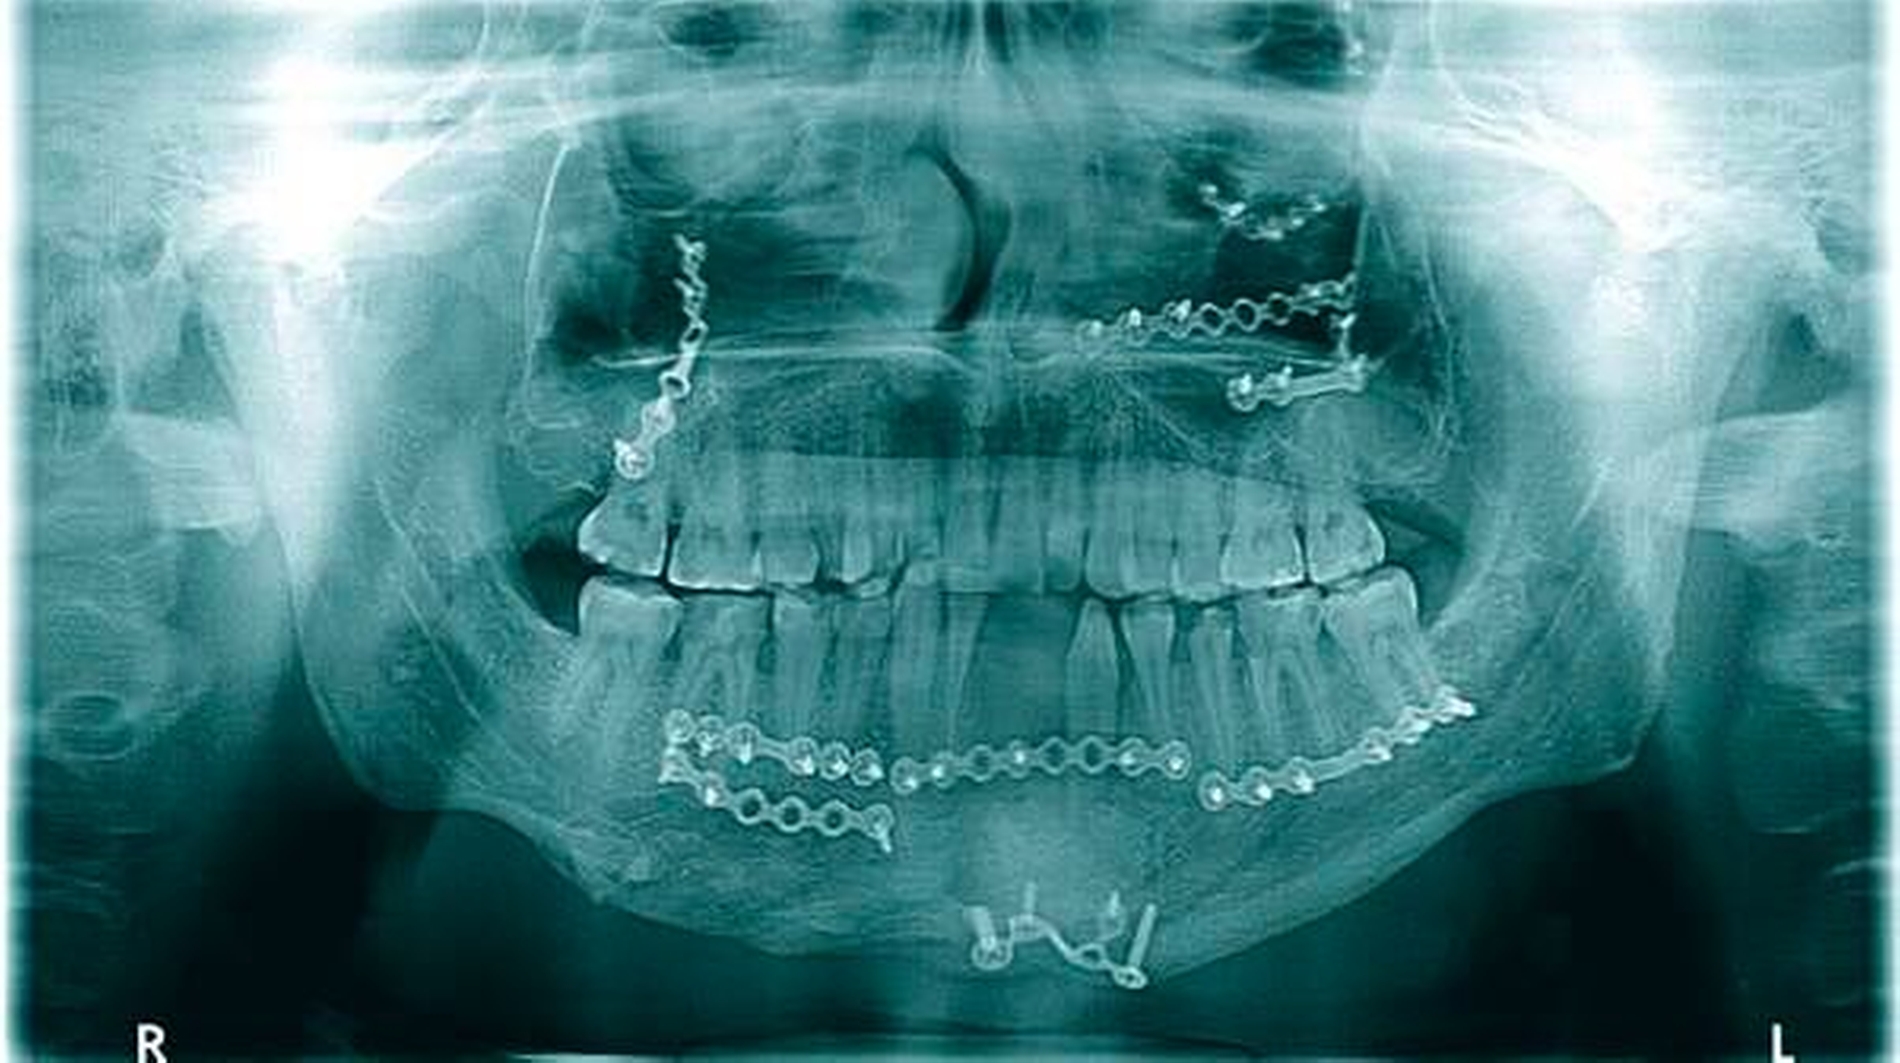

In der Folge entwickelte sich binnen fünf Monaten eine absolute Mundöffnungsbehinderung. Die SKD betrug null Millimeter. Passend zur klinischen Symptomatik zeigten sich radiologisch die Zeichen einer knöchernen Ankylose der Kiefergelenke beidseits Typ III nach Sawhney [1986] (Abbildung 1a bis 1d).